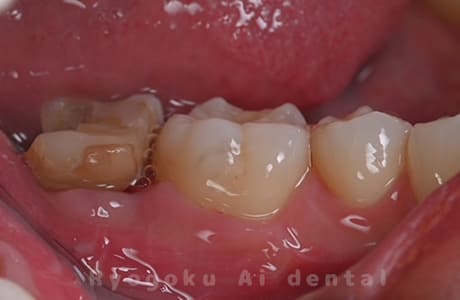

Case09

- 左上6番重度カリエス

- 治療内容

- クラウンレングスニング

-

- 治療費用

- 44,000円(根管治療、補綴は別途費用)

他院で抜歯と判断された歯です。クラウンレングスニングを行い、保存を試みました。現在も問題なく被せ物が入り、使用できてます。

<リスク・副作用>

手術後は痛み、腫れ、痺れ、青あざなどの副作用が生じます。痛みは痛み止めを処方しますが、腫れ、青あざは1週間程度生じる場合があります。また、部位によっては神経の走行が複雑で、痺れが残り、長期的にお薬を処方する場合があります。